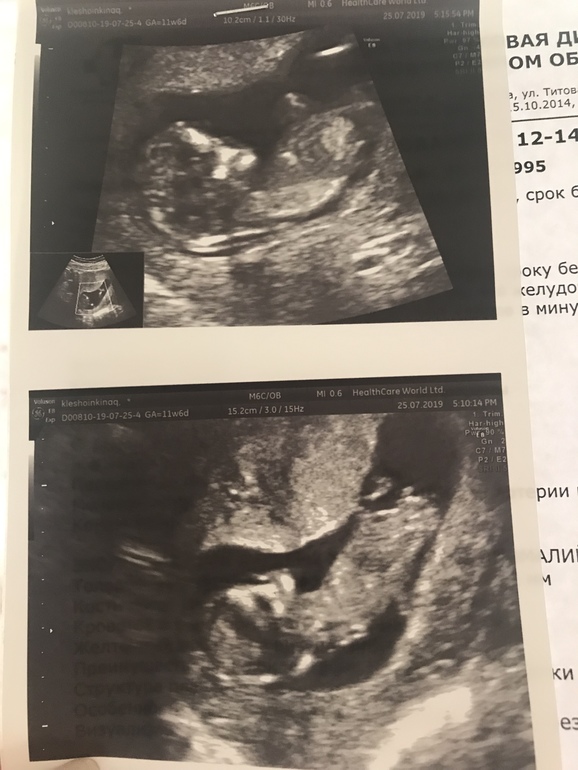

Нет хорошего ракурса, а то, что торчит на 2 фото может быть и не бугорком

2е фото- мальчик больше. Ну если это тг что я думаю. Вдруг бедро)

Мне кажется девочка, т.к. угол между спинкой и половым бугорком менее 30 градусов.

Мне кажется половой бугорок не совсем "лежит" как бывает у девочек, наверно мальчик

Я совсем не спец, но на втором фото вижу что-то похожее на половой бугорок, параллельный позвоночнику. Т.е. я бы сказала "девочка". На верхнем фото полового бугорка не увидела..